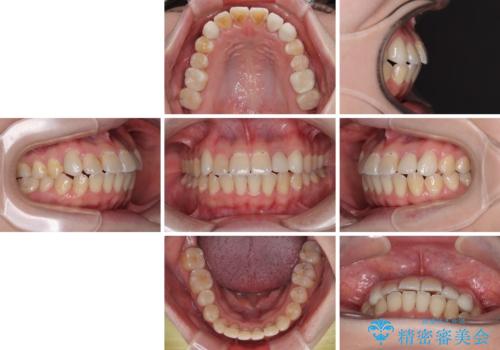

急速拡大が奏効し、非抜歯矯正にて八重歯を解決することができました。

矯正治療後半で結婚式を挙げられたそうですが、参列された方々からは綺麗に整った前歯に大変驚かれたそうで、非常に満足されていらっしゃいました。

矯正治療後は全顎的にむし歯が多いため、セラミッククラウンやインレーにより補綴治療を行うこととしました。